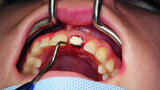

Fig. 1: Single-tooth exposure of tooth #21 after recurrent marginal gingivitis. Owing to the initial diagnosis of extensive resorption, the tooth could not be preserved.

Fig. 2: Initial situation: tooth #21 exhibited marginal redness of the gingiva that bled when probed.